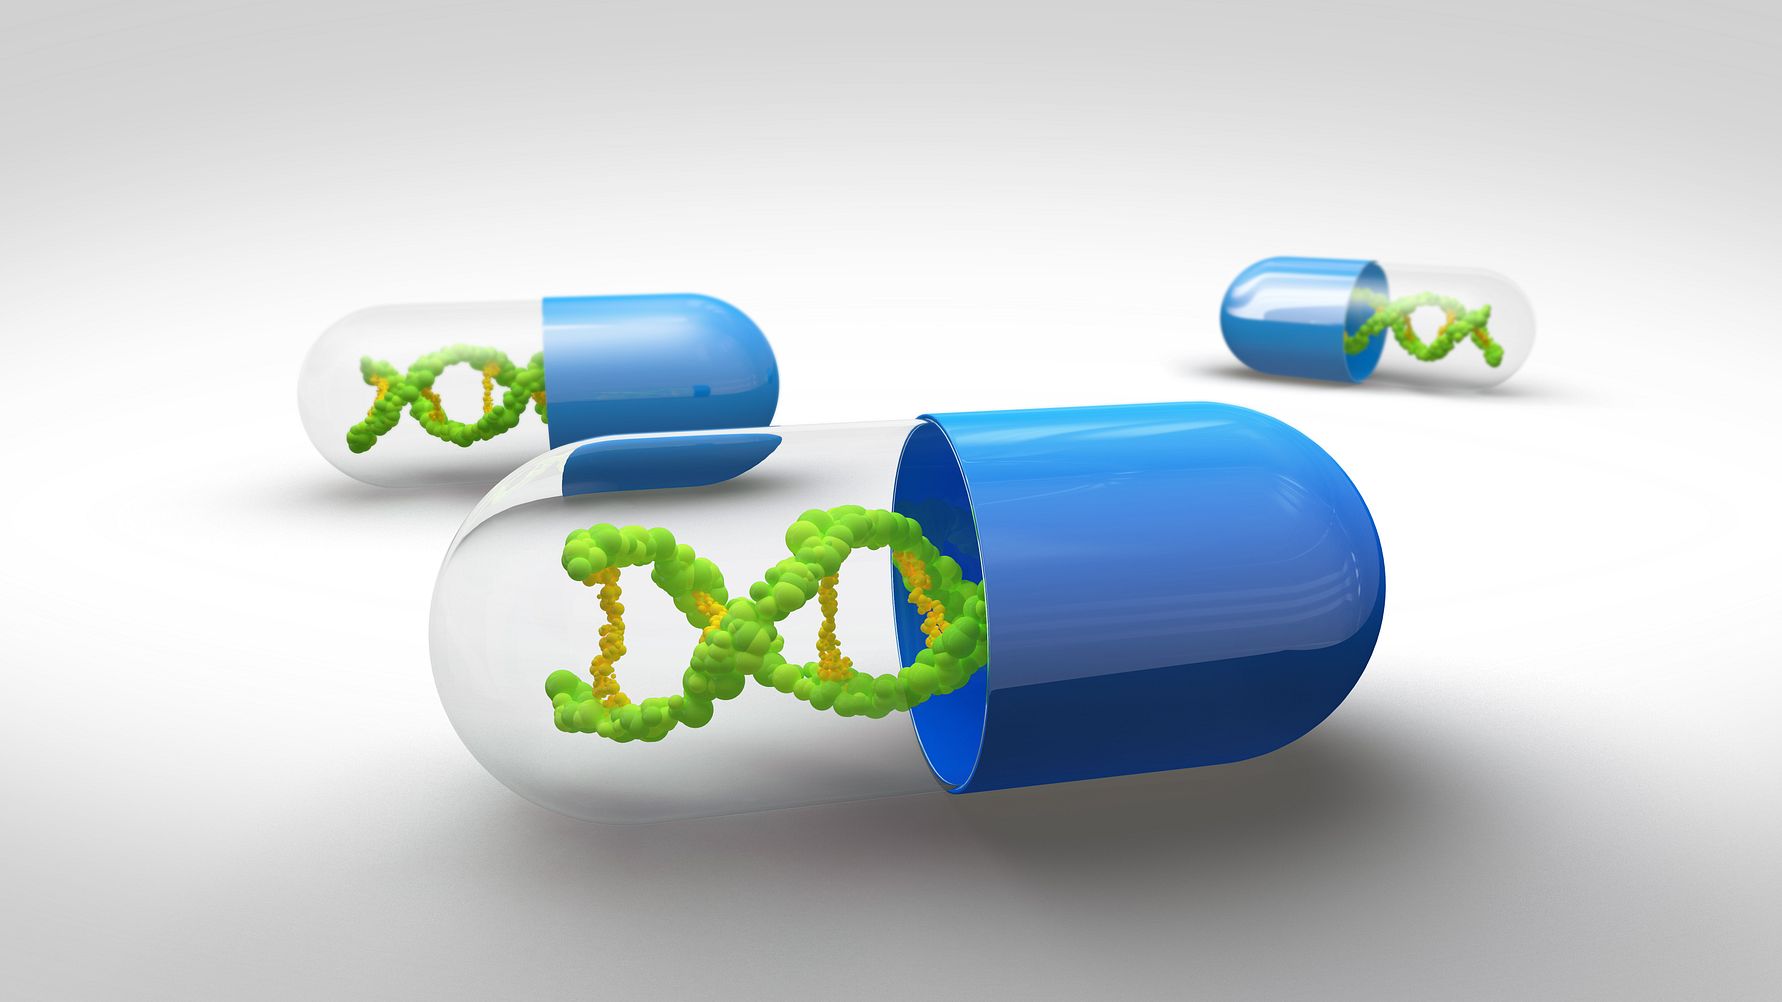

Иллюстрации из Cell Discovery: Удивительный мир науки через фотографии

Раздел: Фотоэссе